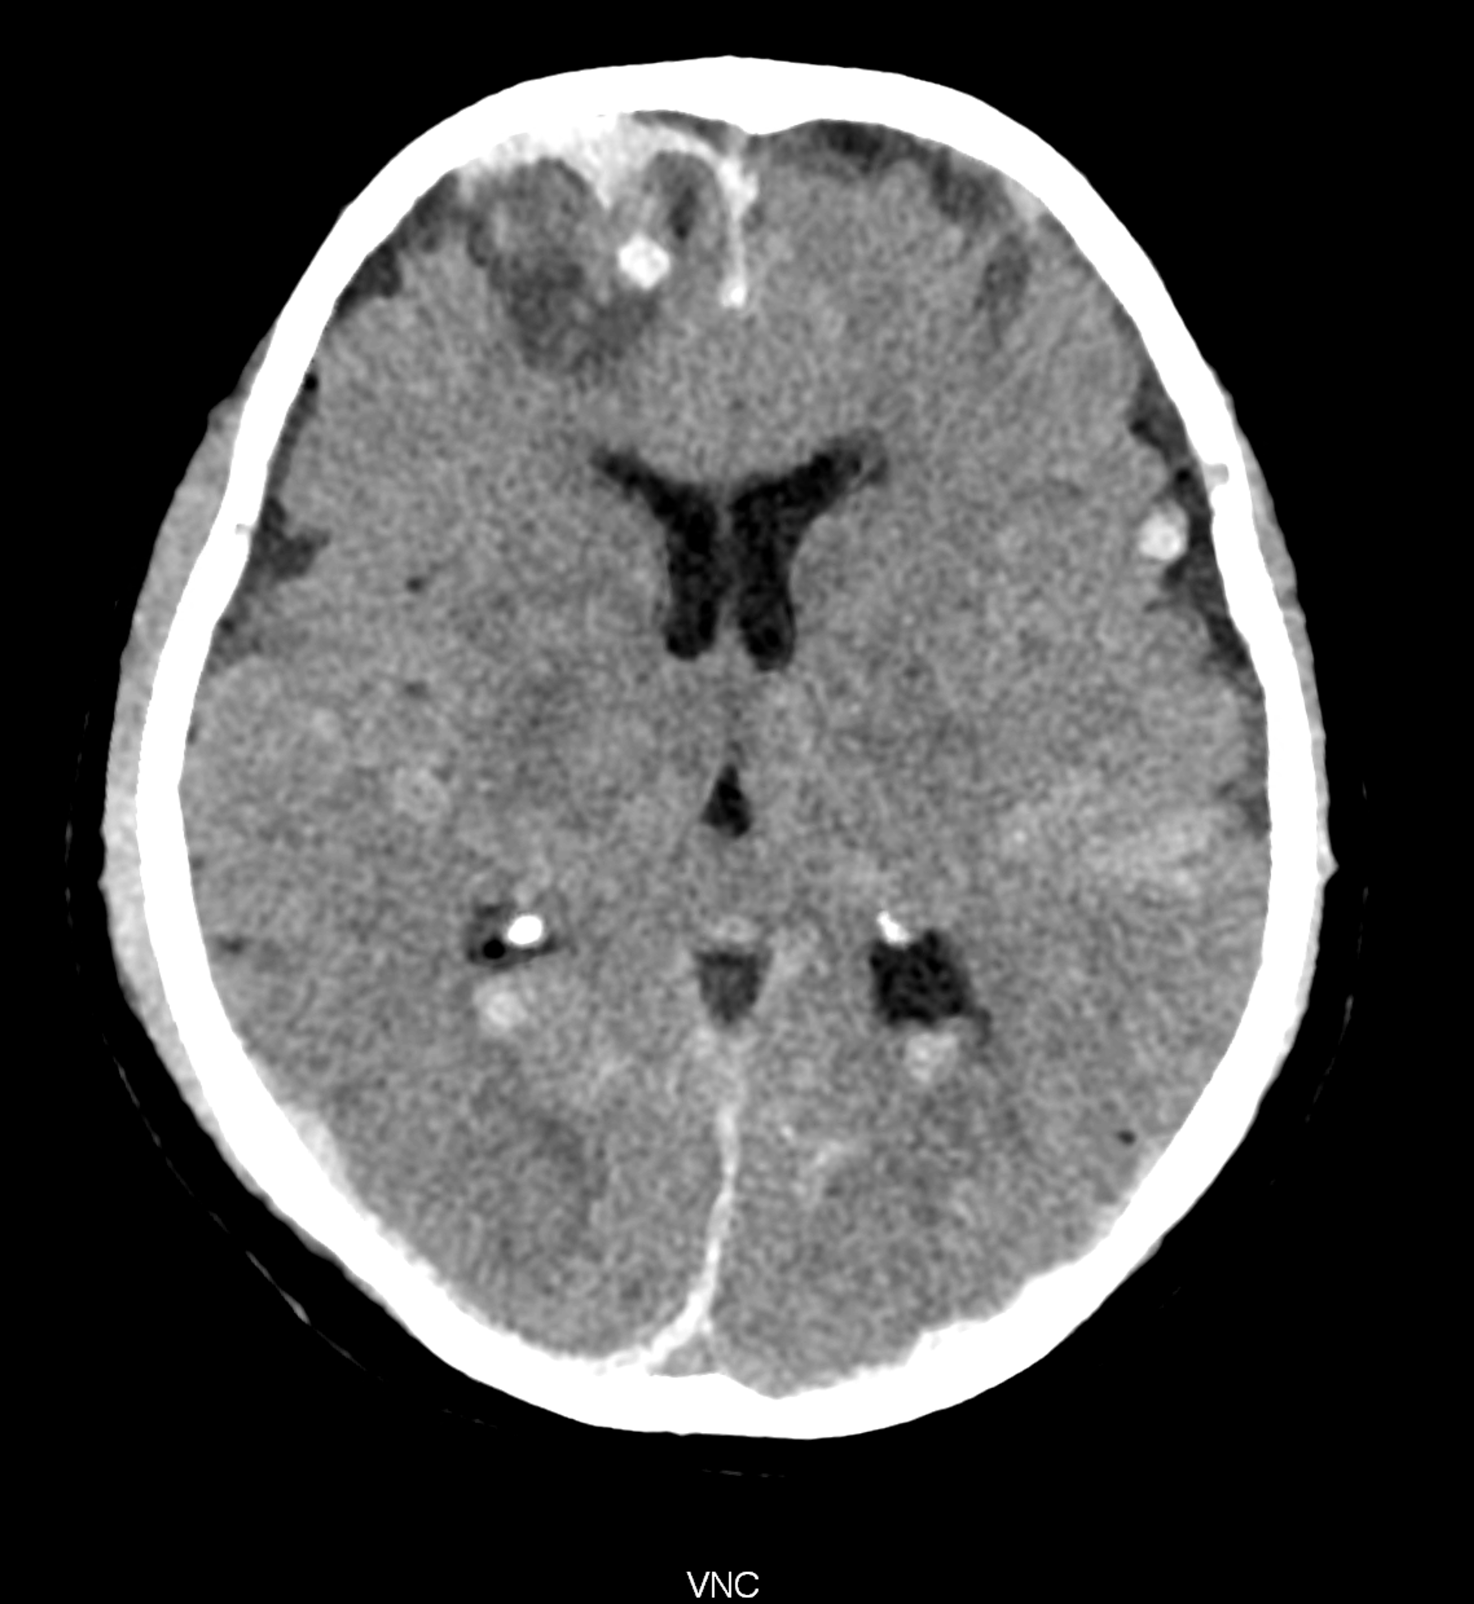

Bleeding is characterized by different absorption characteristics than healthy brain tissue (both gray and white matter) and cerebrospinal fluid. Due to the higher proportion of proteins with amino acids with disulfide bonds, the signal intensity increases at higher energies, making it possible to use monoenergetic imaging at energies above 140 keV, and/or virtual non-contrast. The hemorrhage then becomes more hyperdense, while the rest of the brain tissue acquires a uniform low signal. In addition to bleeding, areas of extracellular fluid of vasogenic origin are also imaged, i.e., in areas around contusion-type brain tissue injuries.

An example of the use of spectral imaging in complex brain injury, where contusions, diffuse axonal injury, subarachnoid hemorrhage, subdural hemorrhage, and blood in the ventricular system are present.

comparison of the images with the energies of monoenergetic reconstructions 40 keV, 67 keV (standard conventional reconstruction), 190 keV and virtual non contrast (VNC)